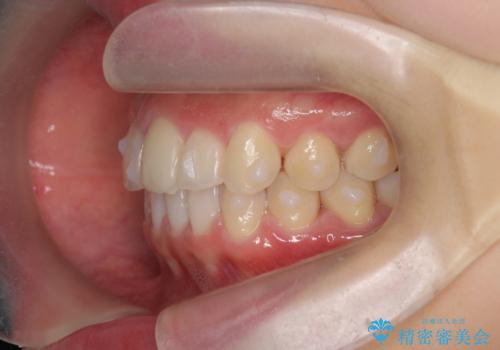

出っ歯に見える前歯の改善 部分ワイヤーとマウスピース矯正

- 出っ歯に見える前歯の改善を希望され、来院されました。

マウスピースでは改善の難しい歯の動きを部分ワイヤー矯正で整えたのち、奥歯の噛み合わせや細かい歯の並びをマウスピース矯正インビザラインで整えていきます。

最終的な前歯の並びに大変満足いただくことができました。